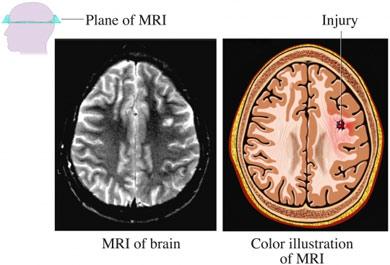

MRI of Brain Injury

© 2009 Nucleus Medical Media, Inc.